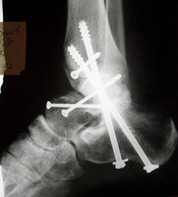

Ваша дискуссия заставила перелистать свои наблюдения.

Среди повреждений таранной кости (Hawkins III-IV) с одновременной травмой лодыжек встретилось следующее (см. вложение). Пациент упал в колодец на глубину 10 метров (Х.2002 г.), госпитализирован с диагнозом: з/перелом шейки правой таранной кости (Hawkins IV) с переломовывихом тела назад и кнутри, закрытый перелом внутренней лодыжки и переднего края большеберцовой кости. Оперирован в первые 12 часов после травмы, выполнена открытая репозиция таранной кости, внутренним и передне-внутренними доступами, остеосинтез переломов шейки и тела губчатыми винтами, для реваскуляризации тела таранной кости первичный компрессионный над- и подтаранный артродез. Синтез внутренней лодыжки губчатым винтом. Удаление винтов через 1 год,2 мес. Получен анкилоз указанных суставов с сохранением длины конечности, полная реваскуляризация таранной кости, о чем говорит сращение ее переломов, отсутствие отеков и

цианоза стопы и голени. Компенсаторная подвижность переднего и среднего отделов стопы около 15-20 градусов за счет поперечного (Шопара) сустава стопы. Считаю оправданной подобную тактику, не смотря на угрожаемый прогноз (100% асептический некроз) по классифицкации Hawkins.